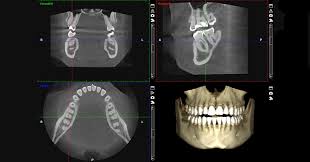

-Tomografía computarizada de haz cónico (Cone beam): Con distintos tamaños de ventana, este estudio permite analizar estructuras dentales y maxilofaciales en los tres planos del espacio sin sobre proyección de estructuras y con ubicaciones espaciales precisas. Solicitado para estudios de zonas para implantes dentales, patologías tumorales y quísticas, localización de dientes retenidos, estudio de senos paranasales, de articulación temporomandibular, evaluación de traumatismos faciales, etc.